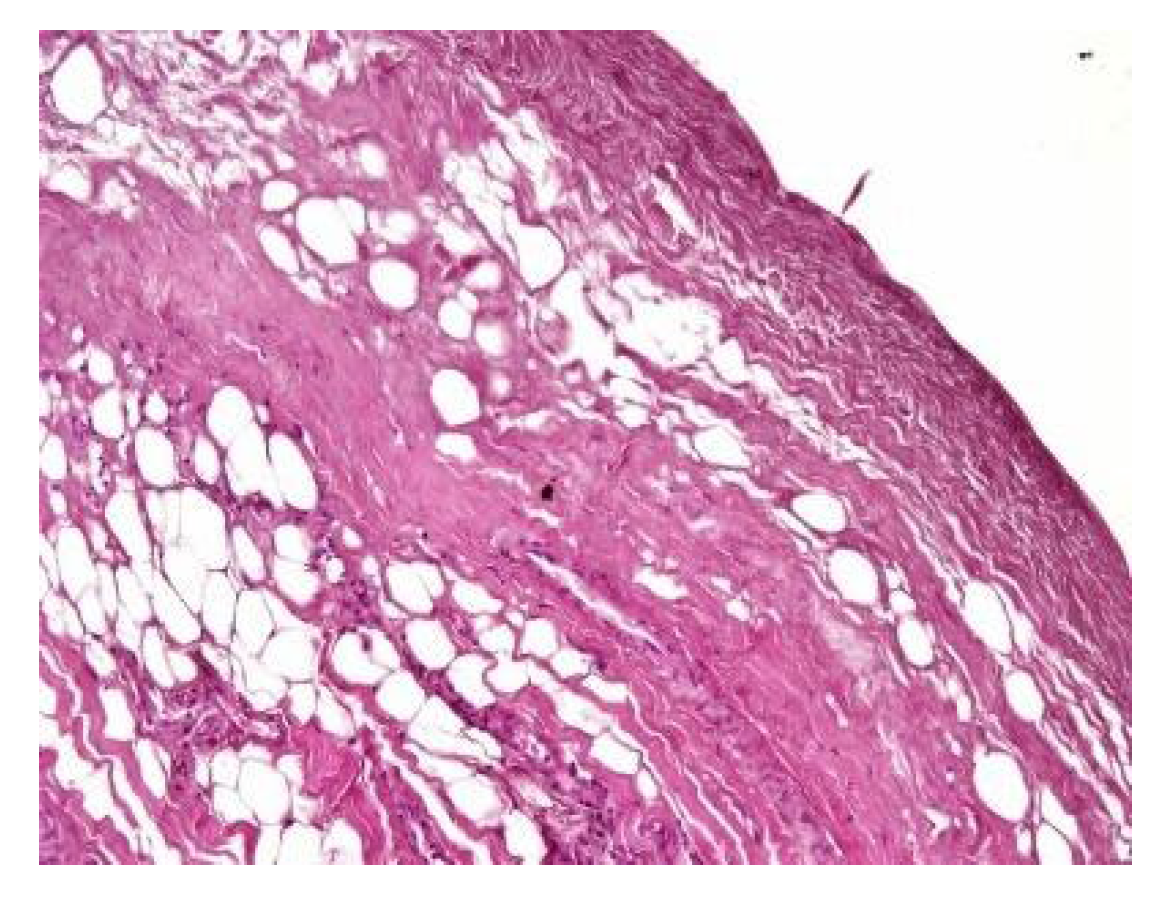

In both of the described cases, optical microscopy revealed lamellar fibrosis, deposits of fibrin on the surface of the peritoneum (Figure 3 and Figure 4) and dystrophic calcifications in the peritoneum (Figure 5 and Figure 6).

Several studies have attempted to identify and/or standardize the morpho-pathological changes in EPS, differentiating it from PS, which is a common occurrence in patients receiving PD and presents as a simple sclerosis [12,13,22,34,35]. The most frequent aspects observed were fibrin deposits, fibroblast swelling and mononuclear cell infiltration [11,12,22]. Garosi et al. investigated 39 biopsies from patients with EPS and found that tissue and arterial calcification, the thickening of the submesothelial layer and vasculopathy were the most significant observed changes [30]. In another study, Sherif et al. found that only fibrin deposits and the thickening of the compacta were significant [36]. In the present study, lamellar fibrosis, decreased cellularity, low grade perivascular inflammation and dystrophic peritoneal calcifications were frequent histological changes. Similarly, Braun et al. attempted to standardize the lesions and to define reproducible histological parameters in patients with EPS. It was found that calcification was a highly indicative criteria for EPS. Furthermore, mesothelial denudation, chronic inflammation, fibrin deposits, decreased cellularity and the presence of fibroblast-like cells were also indicative of EPS [10].

Figure 5. Dystrophic calcifications in the peritoneum (hematoxylin and eosin staining, original magnification × 100).

Figure 6. Dystrophic calcifications in the peritoneum (hematoxylin and eosin staining, original magnification × 100).